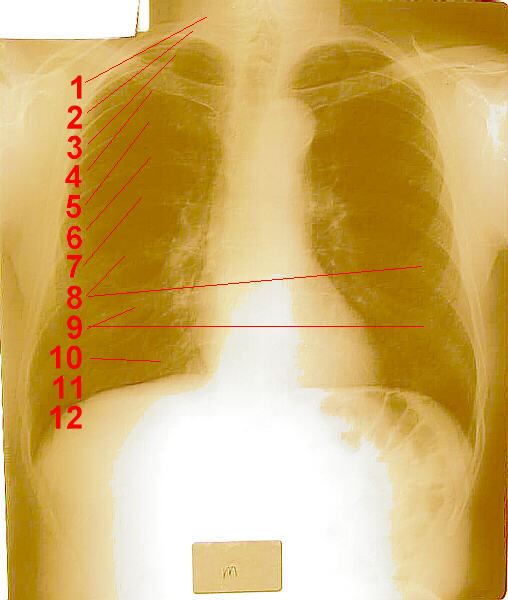

Over the last few years, I have received several e-mail message asking if the number of ribs is different in men and women. To correctly respond to these inquiries, I have researched this issue by looking up this information in several Anatomy and Physiology textbooks. All agree that, based on medical research (somebody actually dissected cadavers and counted ribs, somebody actually looked at x-rays and counted ribs), men and women have the same number of ribs as each other. For example, one book says:

Twelve pairs of flexible, archlike ribs form the lateral portions of the thoracic cage. They increase in length from the first to the seventh and then decrease again from the eighth to the twelfth.

Click on each of these photographs for a larger view.

Female Ribs Male Ribs Male Ribs

X-Ray of Female Ribs X-Ray of Male Ribs Male Skeleton

Unlike people in the Middle Ages, we do science these days (most of the time). We don’t just guess at how many teeth horses have or how many ribs people have. We get in there and count them, and then we know: both men and women have twelve pairs of ribs.